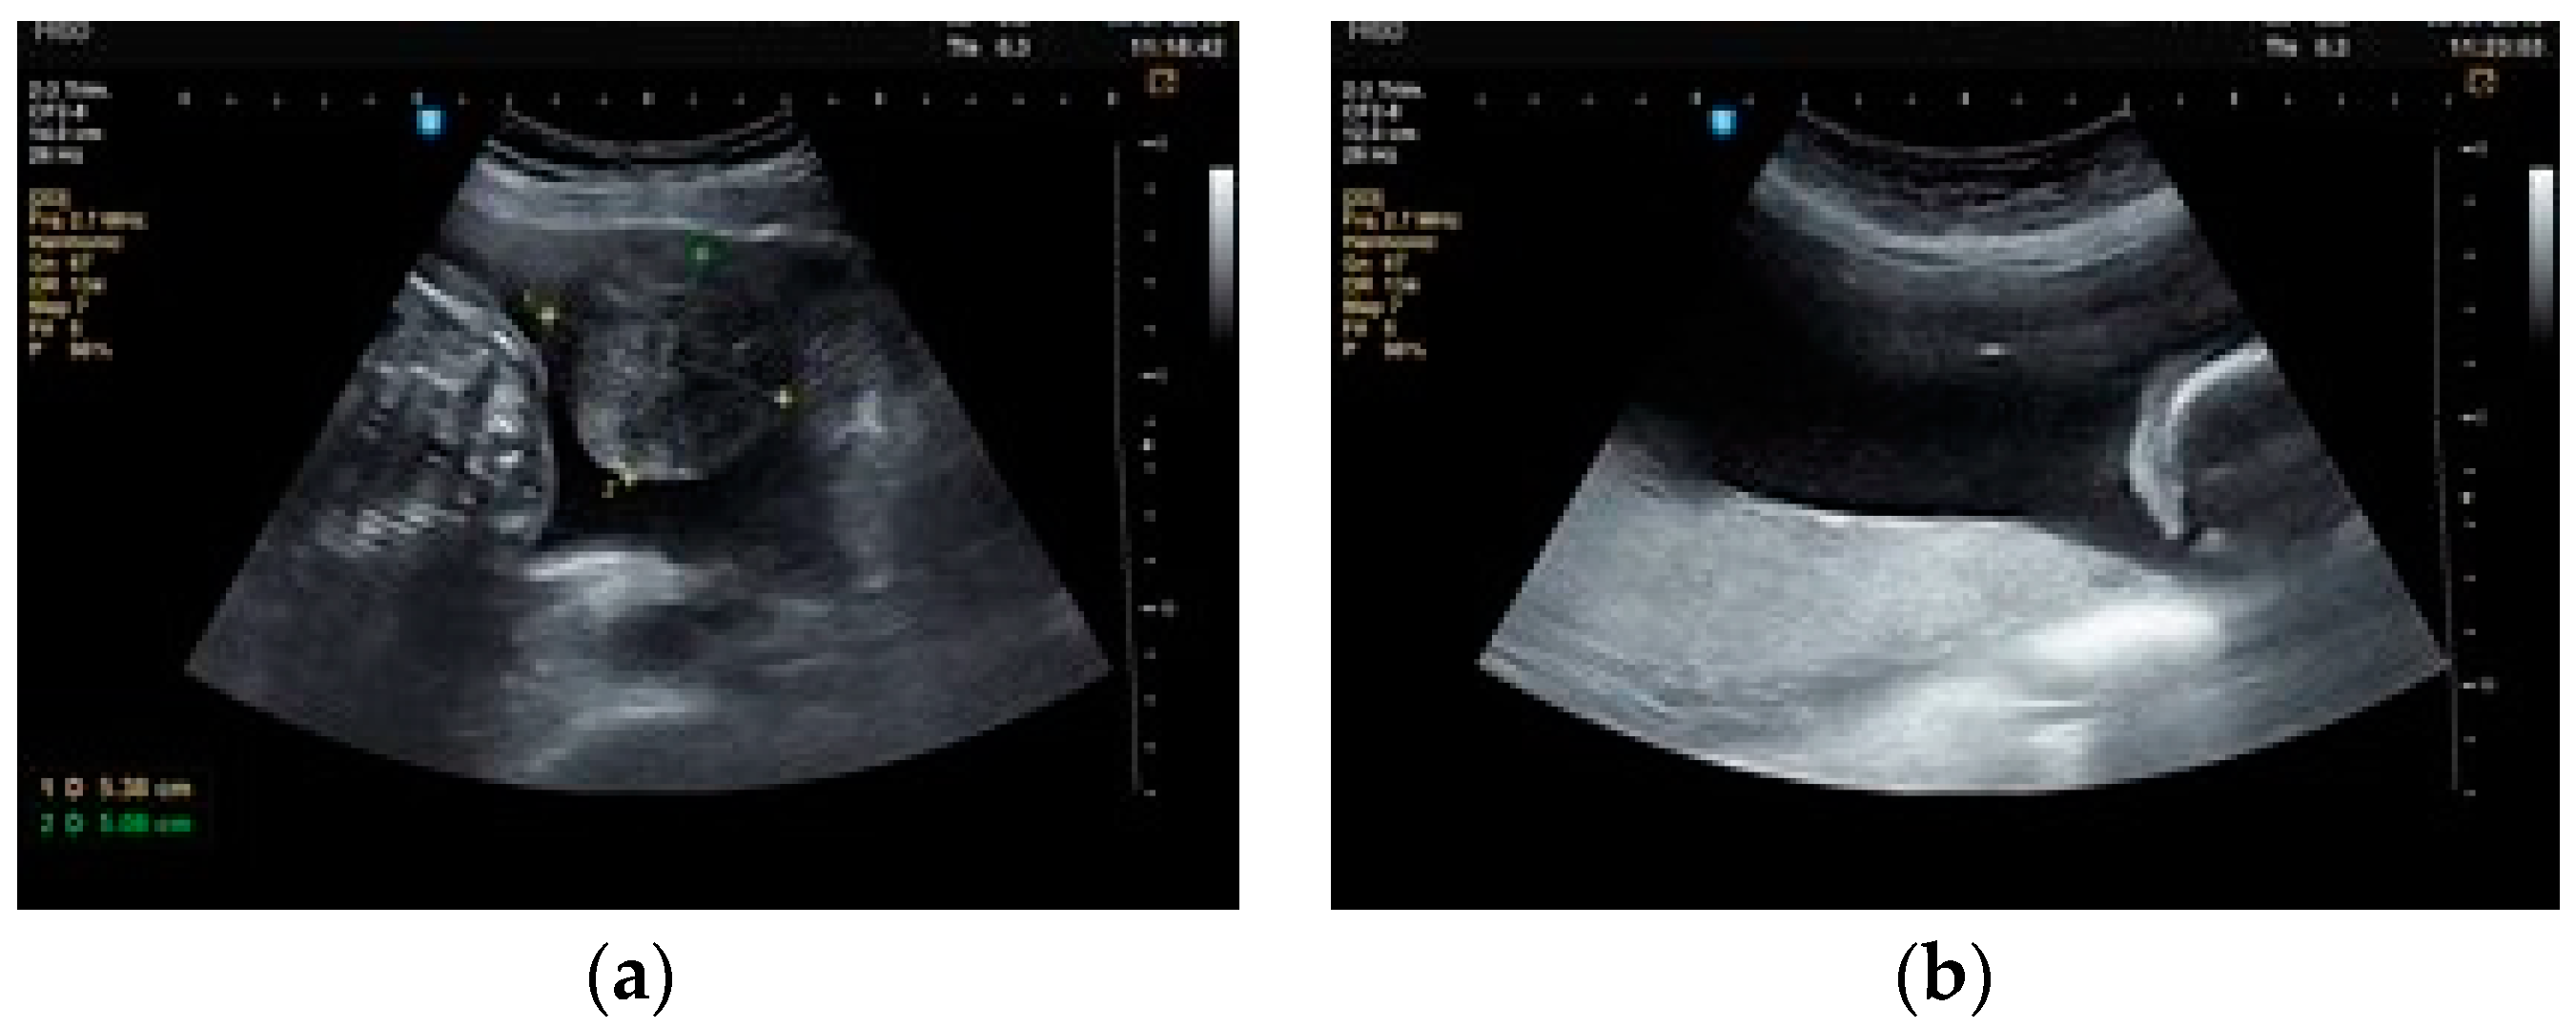

2. Materials and Methods

3. Results